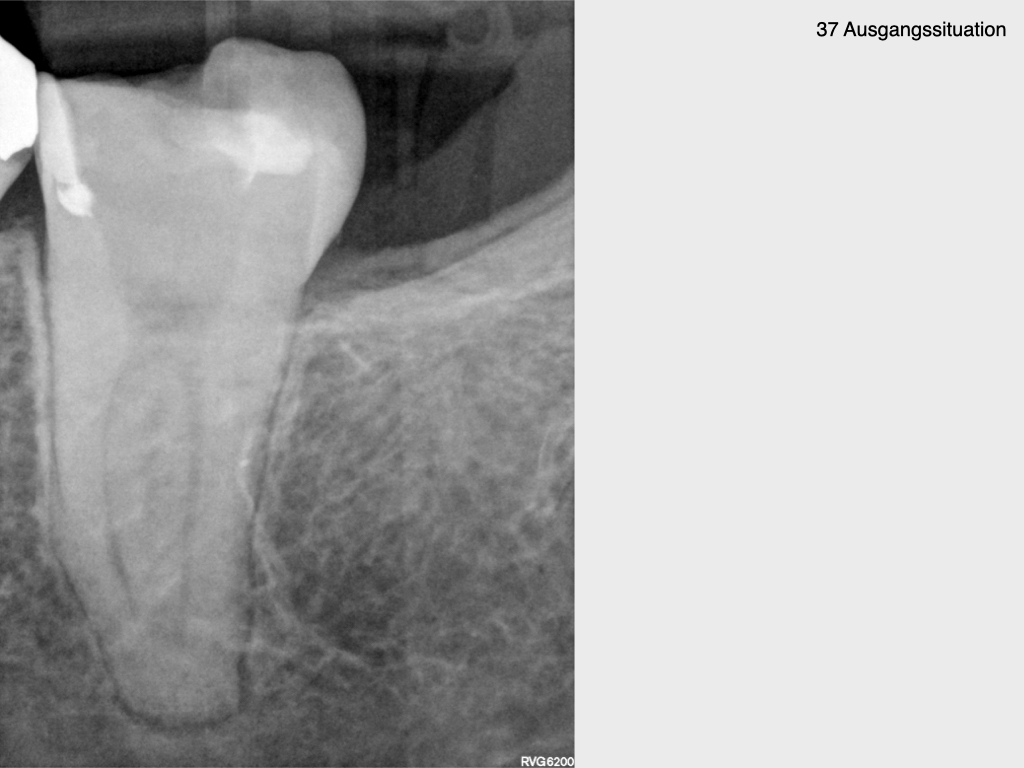

Krampf und Kampf